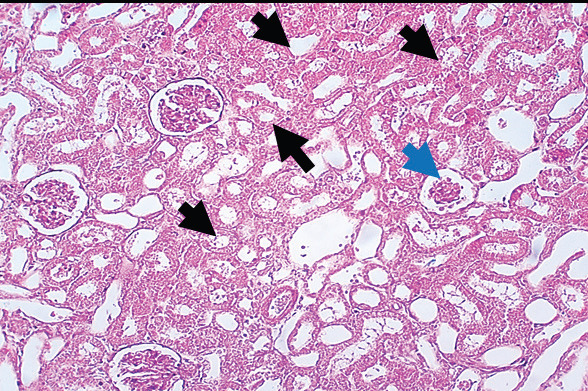

Results: The administration of gentamicin induced a decline in body weight and increases in the levels of inflammatory markers (kidney injury molecule I, tumor necrosis factor-alpha, and interleukin-6), urea, and creatinine, which are indicative of renal damage. Histopathological examination revealed extensive renal tissue damage. However, concurrent administration of gentamicin and GT diminished these parameters by decreasing the malondialdehyde concentration and improving the activity of antioxidant enzymes (glutathione peroxidase and superoxide dismutase). Furthermore, gentamicin injections caused nephrotoxicity, as evidenced by a reduction in body weight and higher levels of urea, creatinine, and inflammatory markers.

Conclusion: GT mitigated the effects of gentamicin by improving the activity of antioxidant enzymes, resulting in a reduction in oxidative stress and minimization of inflammation. These findings suggest a potential complementary role for GT extract in the minimization of gentamicin-induced nephrotoxicity.